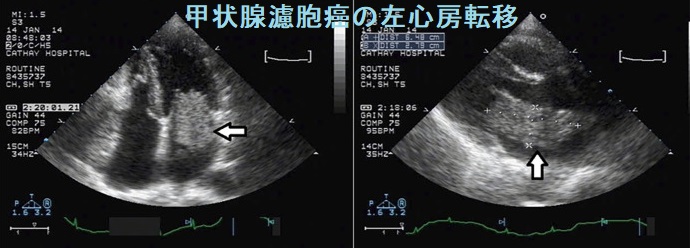

転移部位は右心室が多く、左心室転移は少ない。リンパ行性転移、血行性転移いずれも大静脈から右心室内に至る経路が考えられます。左心系に転移する場合、

- 肺転移巣から肺静脈

- 右心室から肺動脈→肺静脈

を通り、左心系の心内膜に接着・増殖する可能性が考えられます。 (Jpn. J. Clin. Oncol 18:195-201, 1998)

左心房転移による心房細動(Af)で発症した甲状腺濾胞癌の報告があります[J Acute Med. 2020 Mar 1;10(1):45-47.]。